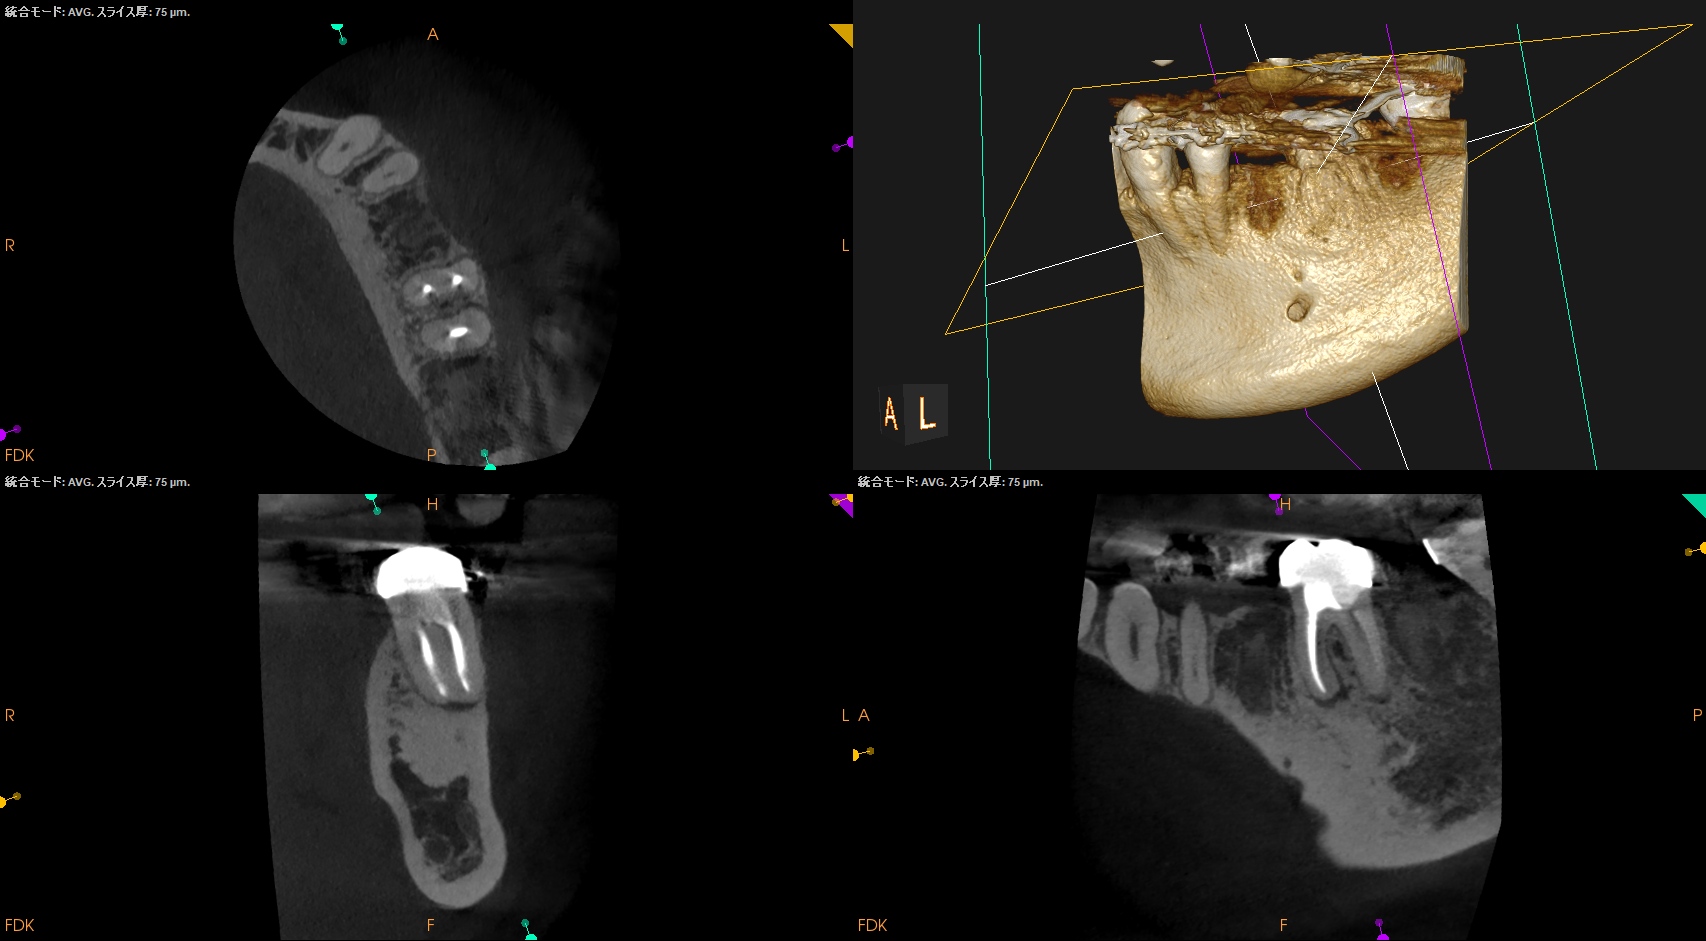

Pre-op CBCT(2025.1.10)

MB

ML

D

根尖病変があるのは近心根のみであるので近心根のみ再根管形成することにした。

その際は、

MBもMLも穿通させる必要があることがCBCTを見える絵にしていけばわかる。